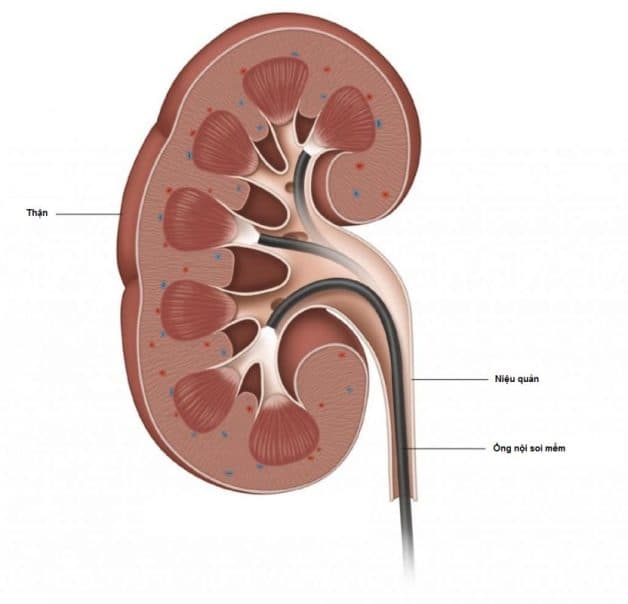

– Tán sỏi nội soi ngược dòng sử dụng ống soi cứng và ống soi mềm: Là phương pháp loại bỏ sỏi hoàn toàn qua đường tự nhiên của cơ thể. Ống nội soi và thiết bị tán sỏi được đưa vào từ lỗ tiểu đến niệu đạo, vào bàng quang, niệu quản và có thể lên xa hơn là thận đối với ống soi mềm. Sỏi sẽ được tán vỡ vụn bằng năng lượng laser thành những mảnh nhỏ và được hút gắp ra bên ngoài. Bệnh nhân ít xâm lấn, ít đau, sau khoảng 24-48h là có thể về nhà.

Tán sỏi nội soi ngược dòng bằng ống mềm laser thực hiện qua đường tự nhiên, không rạch mổ, không để lại sẹo